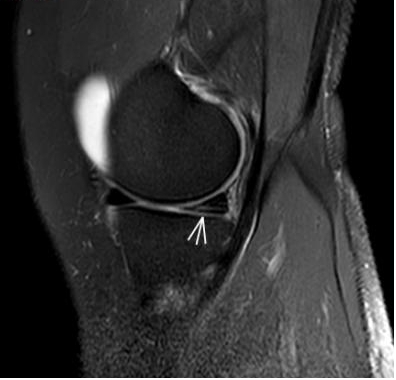

2. 運(yùn)動(dòng)后“打軟腿”——韌帶的“斷弦危機(jī)”

場(chǎng)景:打球急停后膝蓋不穩(wěn),走路像“踩棉花”

MRI偵查:揪出前交叉韌帶斷裂(呈“波浪狀”或連續(xù)性中斷)、內(nèi)側(cè)副韌帶損傷,防止關(guān)節(jié)“脫軌”

(內(nèi)側(cè)副韌帶損傷)